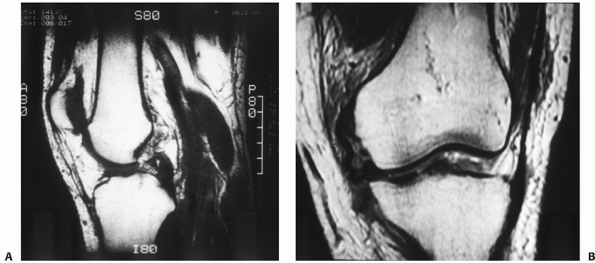

![]() |

|

FIGURE 54-4

Magnetic resonance images of a dislocated knee with complete tears of the medial collateral ligament (MCL), posterior cruciate ligament (PCL), and anterior cruciate ligament with a “peel-off” lesion of the PCL (A) and a tibial avulsion of the MCL on the coronal T1-weighted magnetic resonance image (B). |